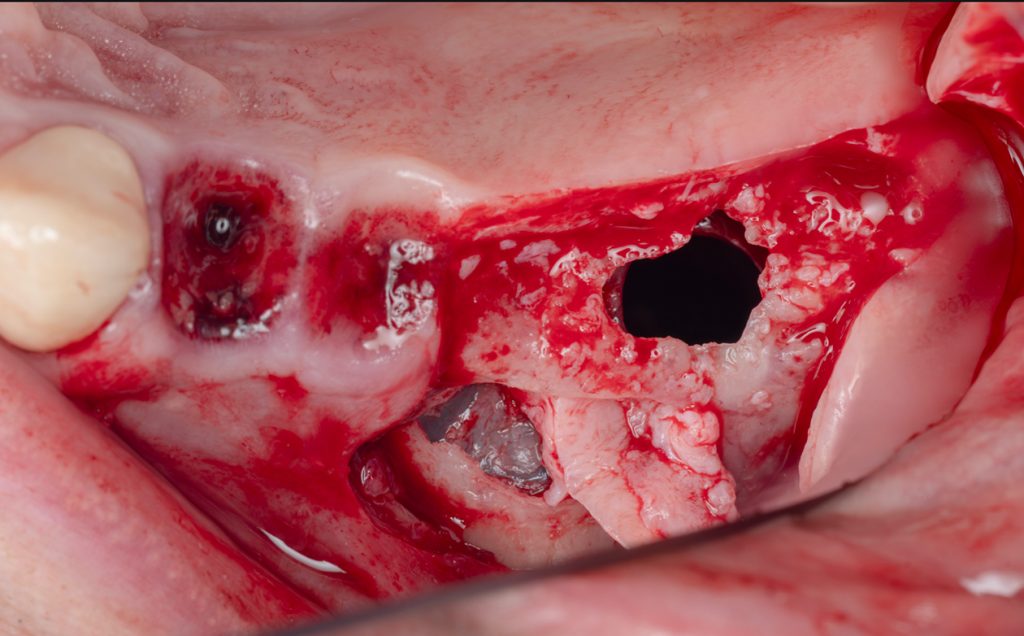

Sinus lift - od kawalifikacji do implantacji

Intensywne szkolenie mentoringowe 1:1, oparte na pracy przypadku klinicznym z pełnym omówieniem diagnostyki, decyzji i przebiegu zabiegu.

Implantacja natychmiastowa w odcinku bocznym i strefie estetycznej

Indywidualny kurs poświęcony implantacji natychmiastowej w odcinku bocznym i strefie estetycznej – oparty na biologii, analizie ryzyka i przewidywalności efektu estetycznego w czasie.

Advanced Bone Reconstruction

Indywidualny szkolenie chirurgiczne dla lekarzy w formule one-to-one, którzy mierzą się z koniecznością implantacji w warunkach niedoboru kości i chcą podejmować decyzje świadomie, bez kompromisów biologicznych.